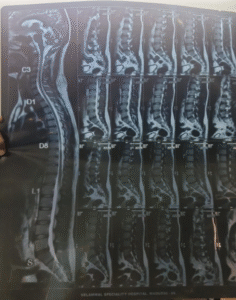

• MRI of the whole spine

• Normal. No abnormalities

• CT of the spine

• No abnormalities

mri whole spine

• MRI also normal – there are no impressions of sacroiliitis

• MRI and CT spine were normal, ruling out structural abnormalities. No red flag signs were present.